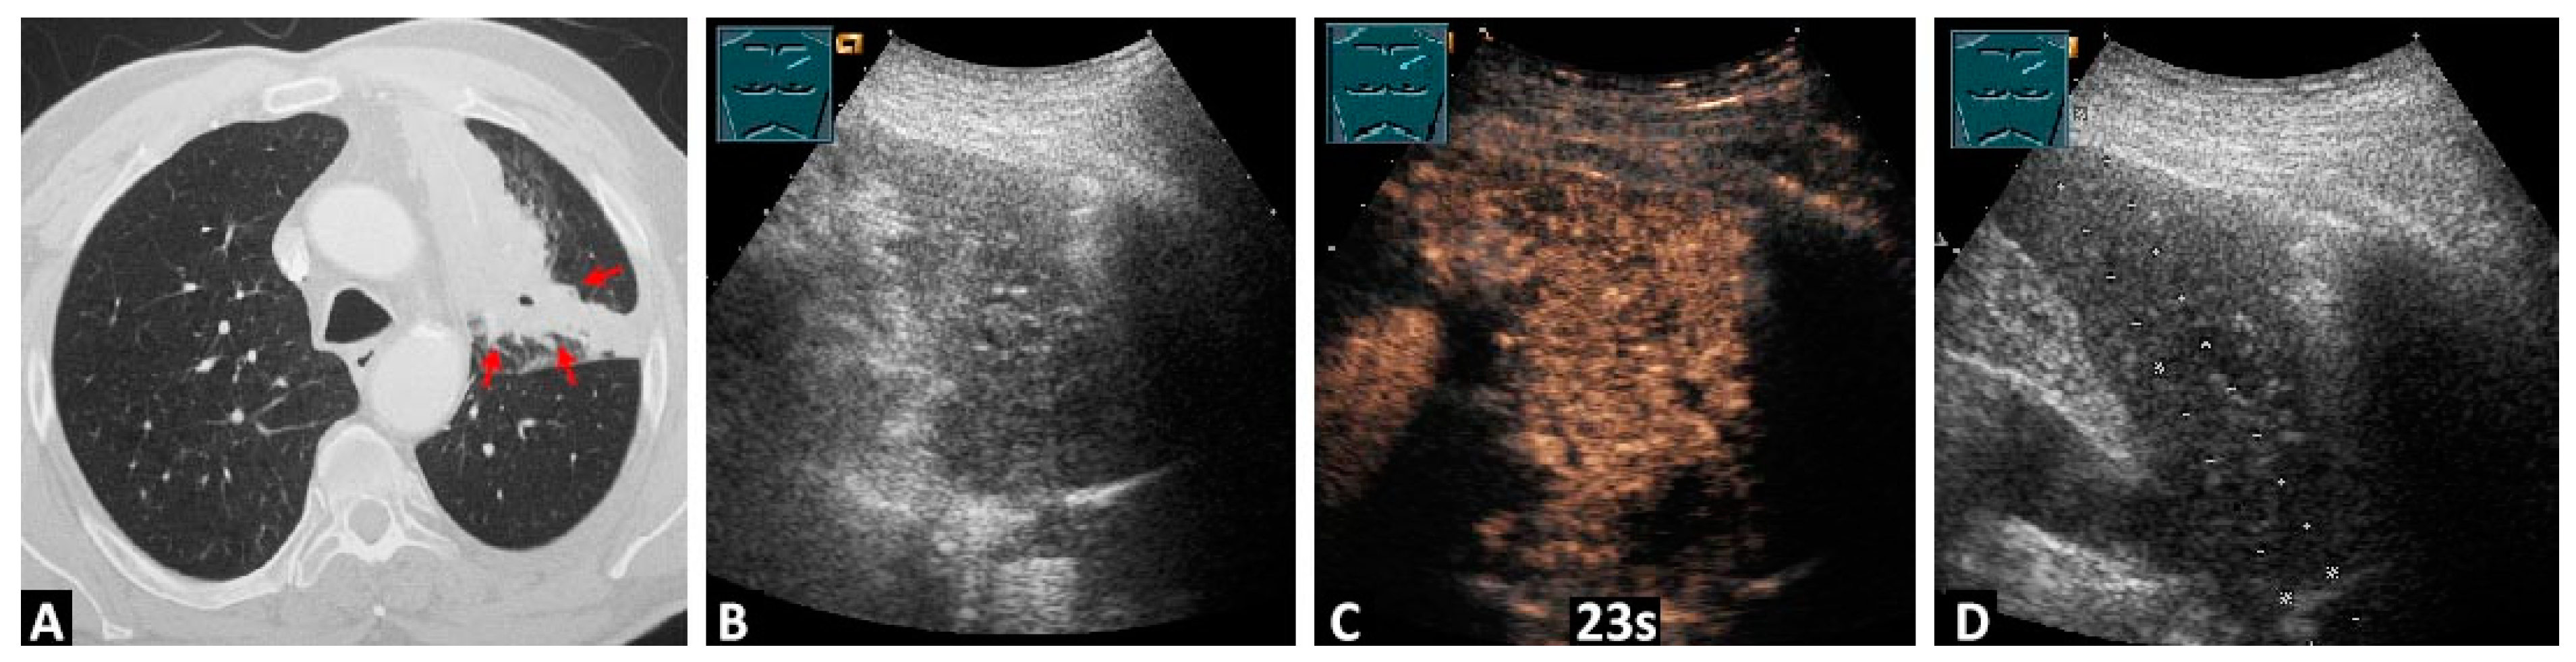

3.2.1. Differentiation between the Tumor and Atelectatic Tissue on B-US

3.3.1. Differentiation between the Tumor and Atelectatic Tissue on CEUS